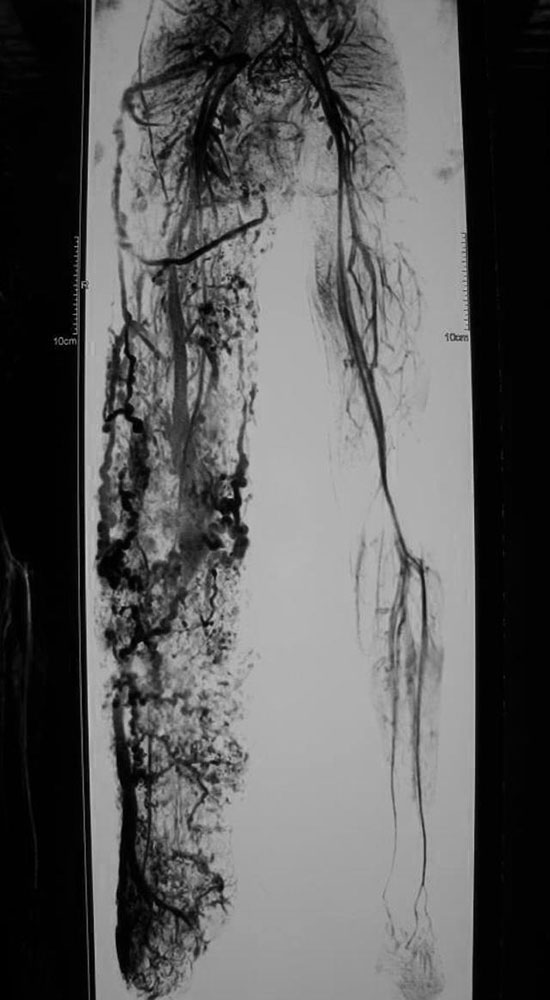

Contrary to earlier assumptions, it is not the malformed vessels but concomitant primary dysplasia of the soft tissue that is responsible for the overgrowth. The vascular anomalies extend over the affected body side with a predilection for the lateral parts. While the capillary malformation may become less conspicuous and is sometimes only recognizable from the reticular veins that have developed secondarily as outflow vessels, the venous malformation increases in size over the years. Subcutaneous vessels of large caliber on the outside of the leg enter the deep venous system at the knee, thigh or gluteal level. Although this venous malformation is referred to as a marginal vein or embryonic vein when there is aplasia of the deep veins, the existing vascular morphology often corresponds more to a venous plexus than a singular vessel.